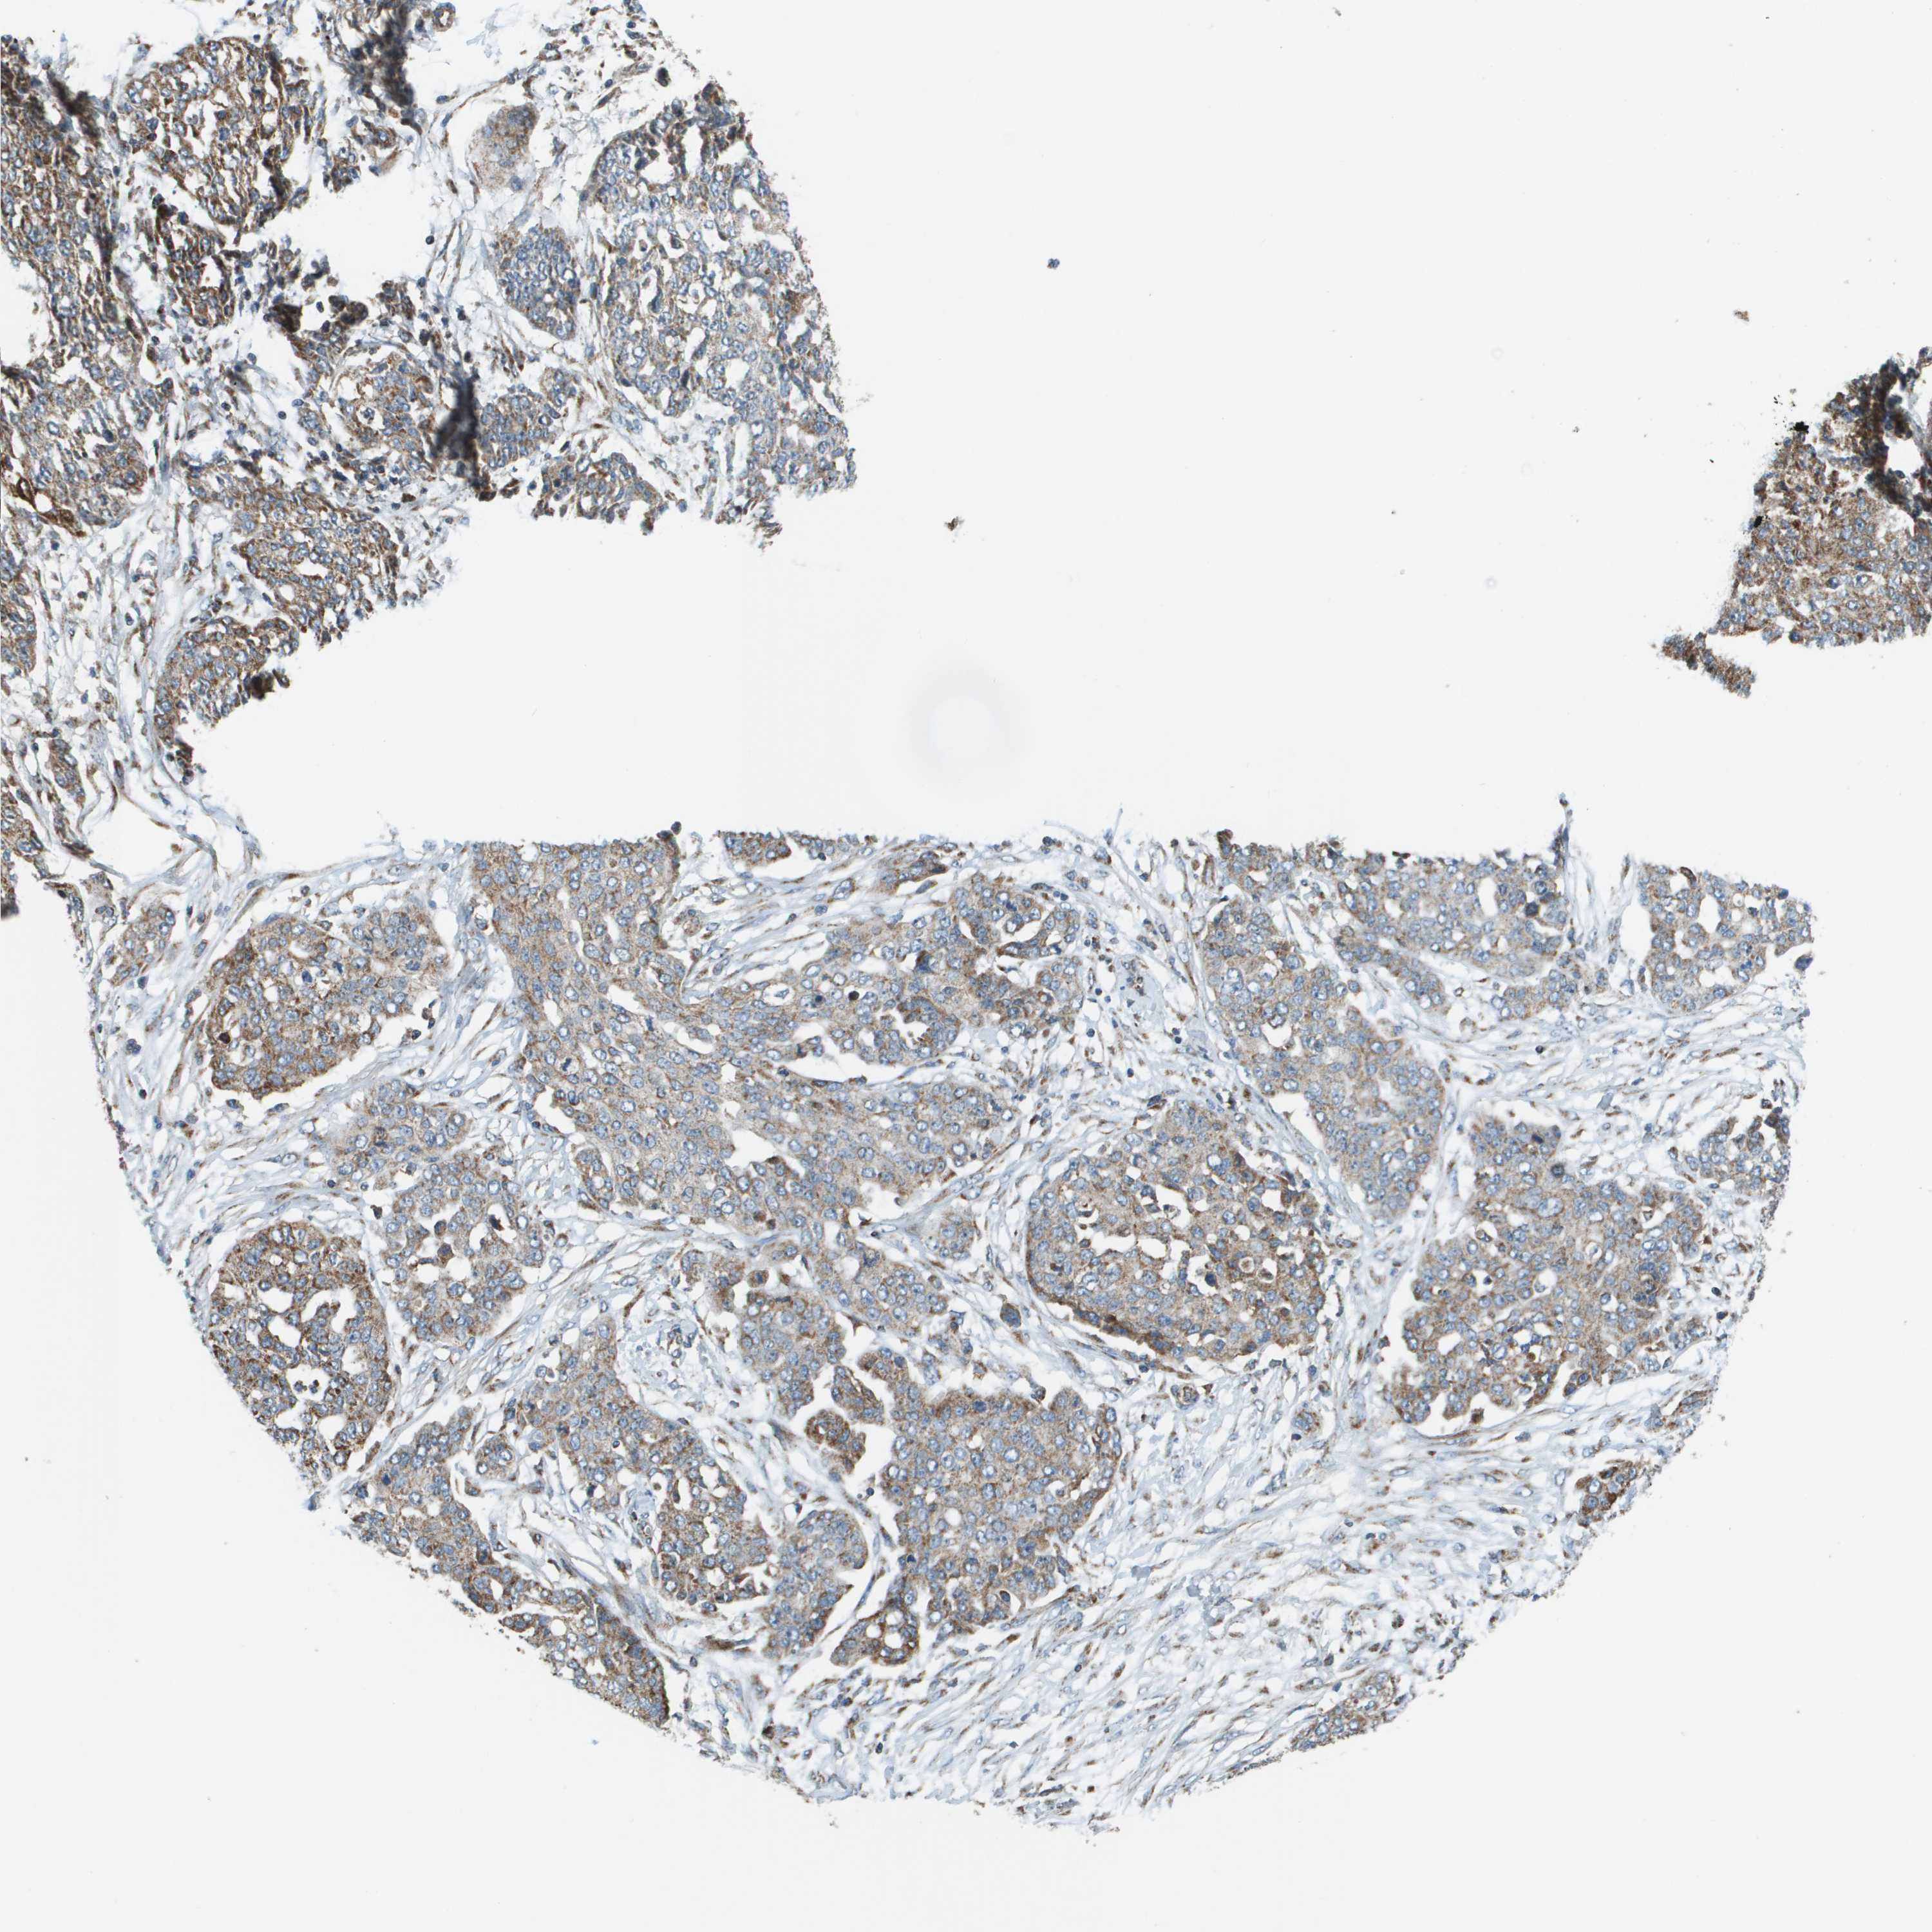

OVARIAN CANCER - Protein expressioni

A mouse-over function shows sample information and annotation data. Click on an image to view it in a full screen mode. Samples can be filtered based on level of antibody staining by selecting one or several of the following categories: high, medium, low and not detected. The assay and annotation is described here.

Note that samples used for immunohistochemistry by the Human Protein Atlas do not correspond to samples in the TCGA dataset.

Antibody stainingi

Antibody staining in the annotated cell types in the current human tissue is reported as not detected, low, medium, or high, based on conventional immunohistochemistry profiling in selected tissues. This score is based on the combination of the staining intensity and fraction of stained cells.

Each image is clickable and will lead to virtual microscopy that enables deeper exploration of all samples and also displays staining intensity scores, fraction scores and subcellular localization as well as patient and tissue information for each sample.

Antibody HPA017238

Cystadenocarcinoma, serous, NOS

Carcinoma, endometroid

Cystadenocarcinoma, mucinous, NOS

Carcinoma, NOS